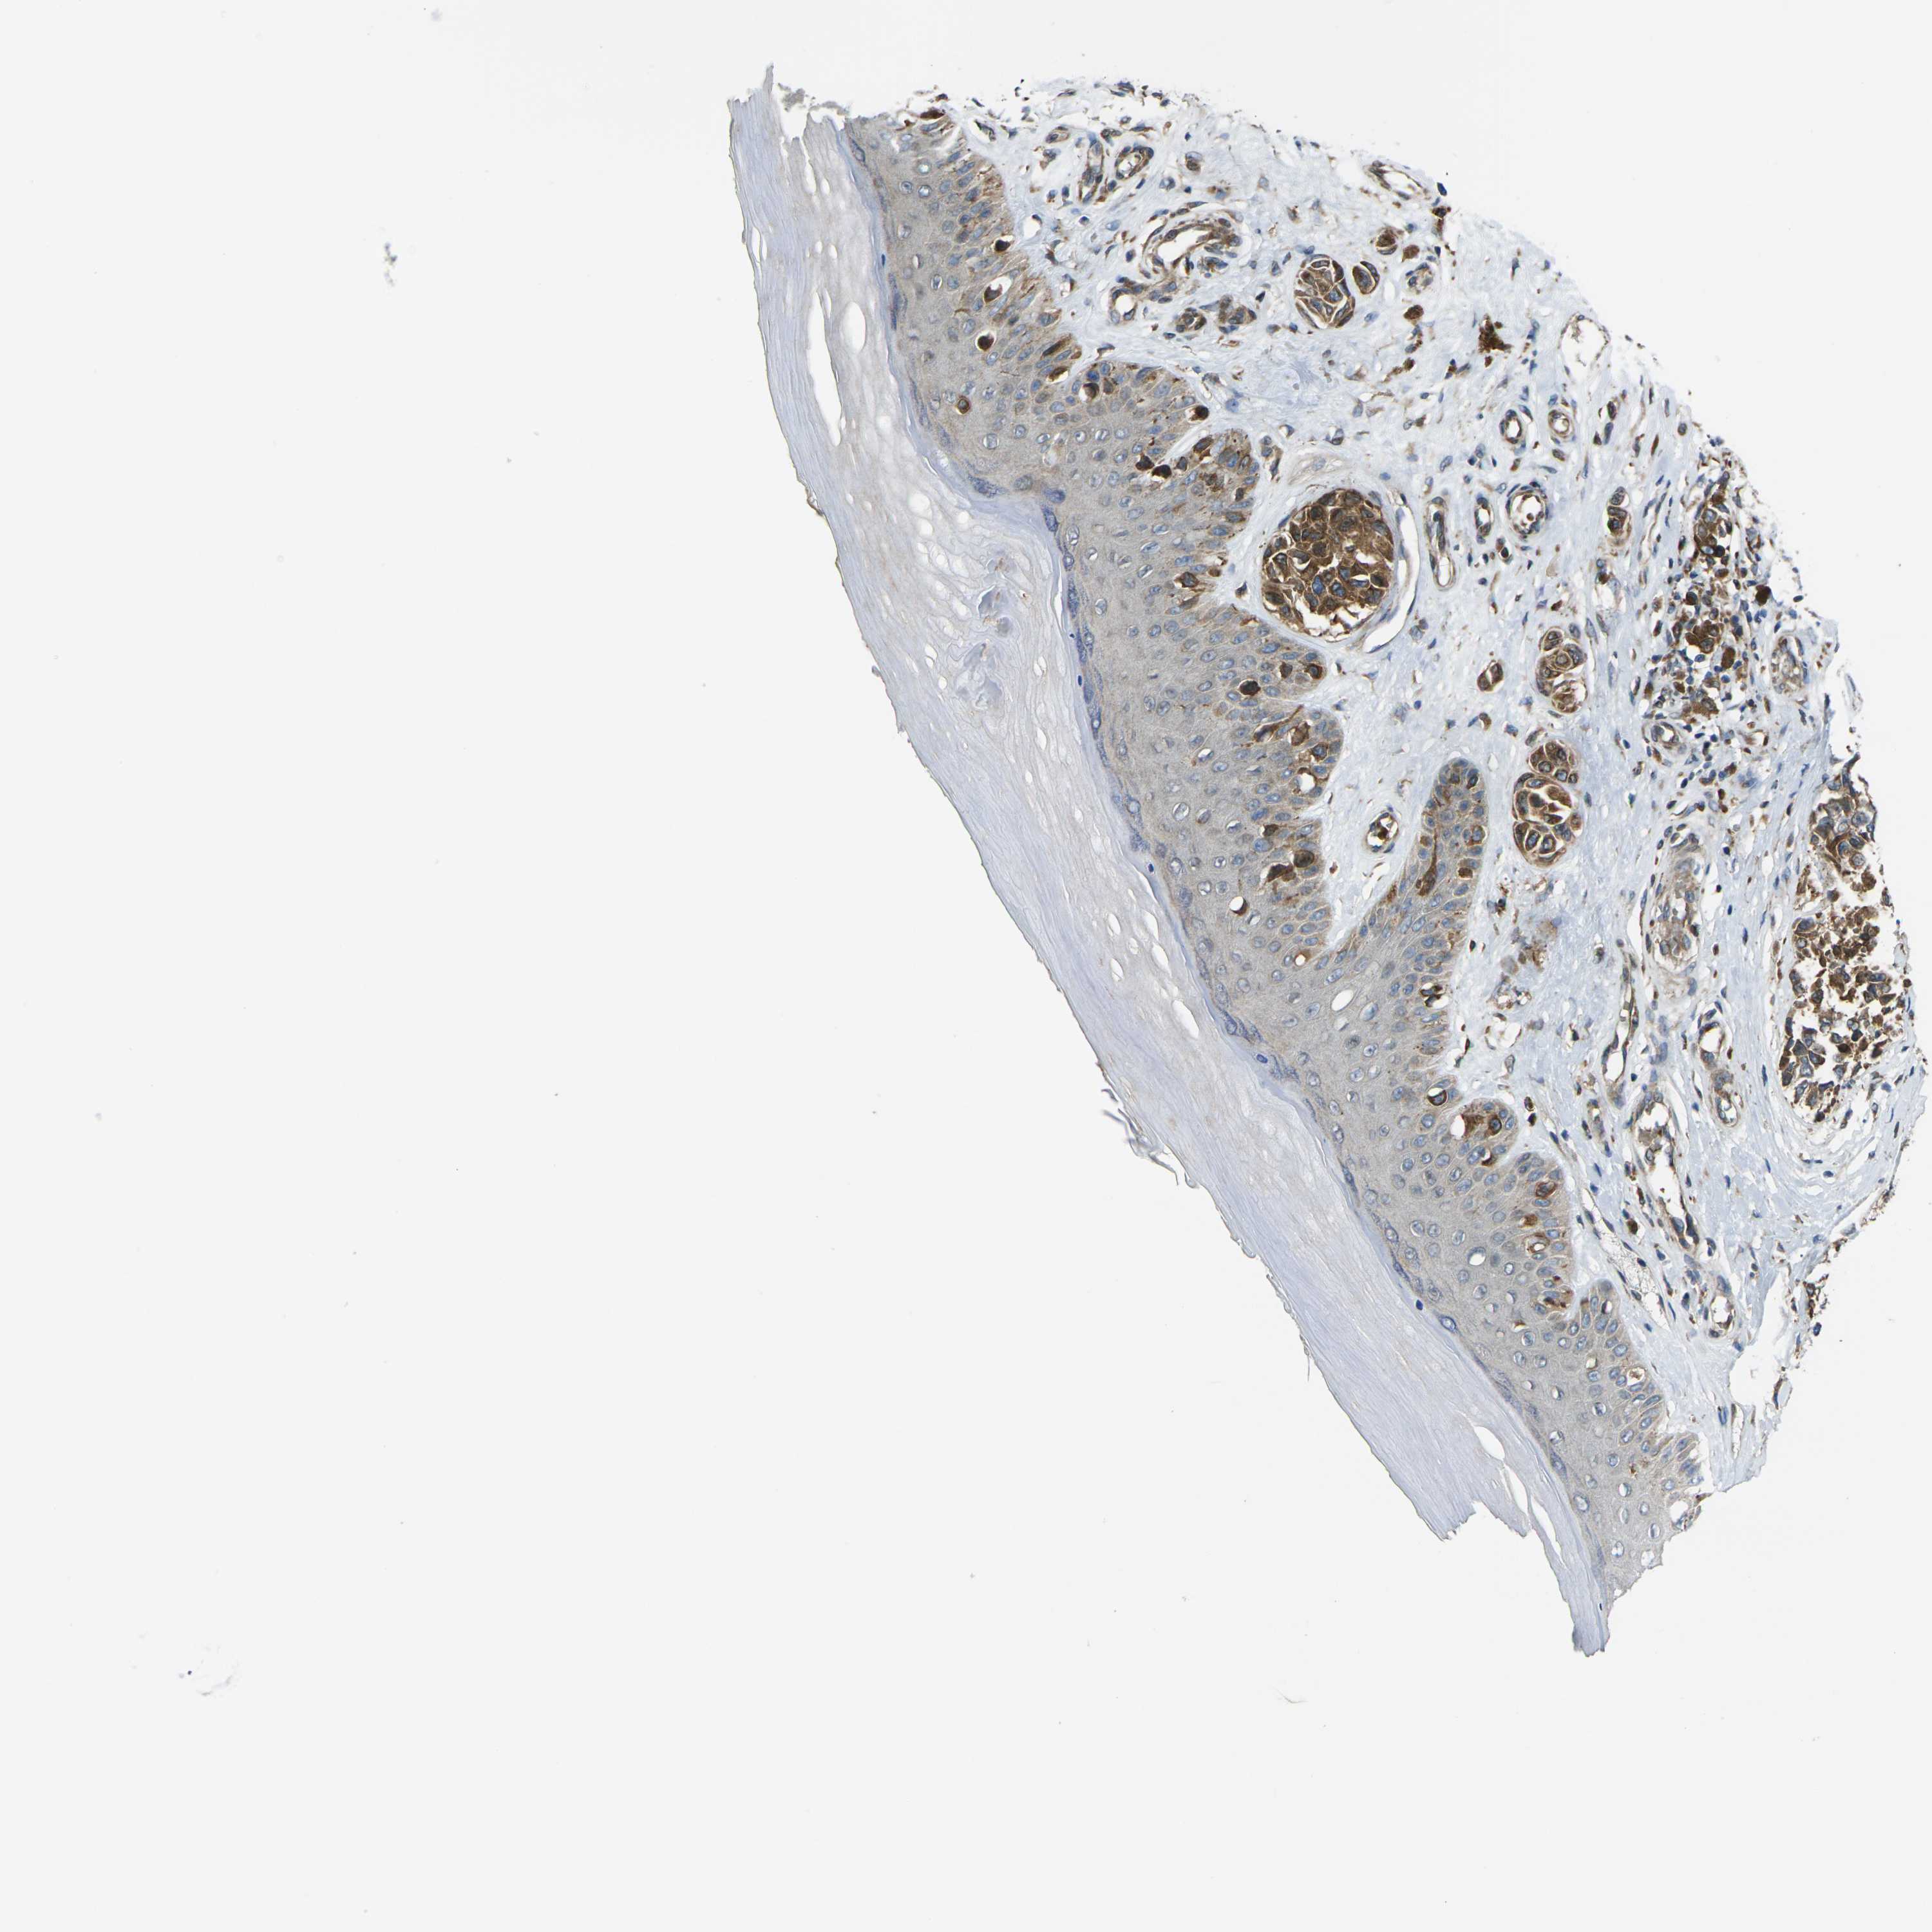

MELANOMA - Protein expressioni

A mouse-over function shows sample information and annotation data. Click on an image to view it in a full screen mode. Samples can be filtered based on level of antibody staining by selecting one or several of the following categories: high, medium, low and not detected. The assay and annotation is described here.

Note that samples used for immunohistochemistry by the Human Protein Atlas do not correspond to samples in the TCGA dataset.

Antibody stainingi

Antibody staining in the annotated cell types in the current human tissue is reported as not detected, low, medium, or high, based on conventional immunohistochemistry profiling in selected tissues. This score is based on the combination of the staining intensity and fraction of stained cells.

Each image is clickable and will lead to virtual microscopy that enables deeper exploration of all samples and also displays staining intensity scores, fraction scores and subcellular localization as well as patient and tissue information for each sample.

Antibody CAB013008

Staining

High

Medium

Low

Not detected

Intensity

Strong

Moderate

Weak

Negative

Quantity

>75%

75%-25%

<25%

None

Location

Nuclear

Cytoplasmic/membranous

Cytoplasmic/membranous,nuclear

Malignant melanoma, NOS

Malignant melanoma in situ

Malignant melanoma, Metastatic site